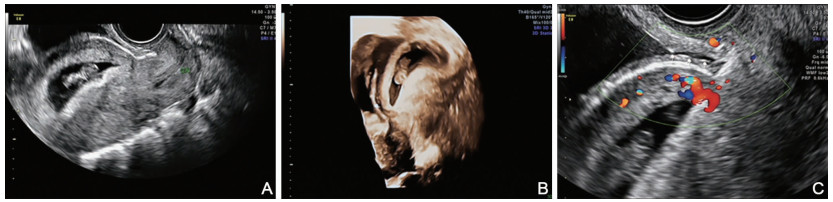

Significance of ultrasound examination in the evaluation and treatment of uterine scar pregnancy

SHI Cai-hong, LIU Xue-ge, MENG Hui-yan, WEI Yue-liu

2021, 19(2): 283-286. doi: 10.16766/j.cnki.issn.1674-4152.001789

919 4

Abstract:

Objective  To explore the ultrasonographic characteristics, surgical methods and postoperative recovery of different types of cesarean scar pregnancy (CSP) patients.  Methods  Ninety-two cases of CSP diagnosed and treated in our hospital from January 2015 to December 2018 were analysed. The general clinical data, ultrasonographic features, operation and postoperative recovery were compared. The data were analysed by SPSS 23.0 statistical software.  Results  A total of 92 CSP patients were divided into 28 cases of type Ⅰ, 45 cases of type Ⅱ and 19 cases of type Ⅲ. No significant difference in age, menopause time, distance from the last caesarean section and serum β-HCG content was found before treatment (all P>0.05), but a significant difference in the number of induced abortion and caesarean section was observed (all P < 0.05). Significant differences in the thickness of the anterior inferior segment of the uterus, the percentage of villus invading the myometrium, the percentage of small amount of blood flow and rich blood flow in Alder classification were found (all P < 0.05). Moreover, statistical differences in the ratio of type A operation to type B operation and hospitalisation time were observed (all P < 0.05). However, no significant difference in the time when β-HCG dropped to normal was observed (P>0.05).  Conclusion  There are some differences in the general clinical, ultrasonic features, surgical methods and postoperative recovery of CSP patients with different ultrasonic classification. Ultrasound examination has certain guiding value for the classification of CSP and the selection of surgical methods.